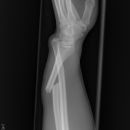

Unterarmschaft Fraktur

Monteggia-Fraktur

Galeazzi-Fraktur